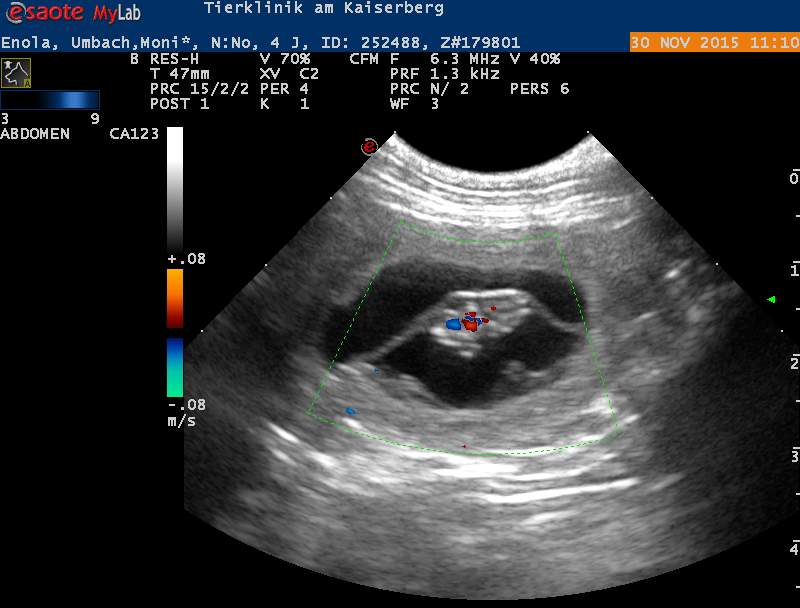

Ultraschallbild (Beweisfoto)

Am 30.11.2015 wurde von Dr. Kresken die Trächtigkeit von Enola bestätigt.